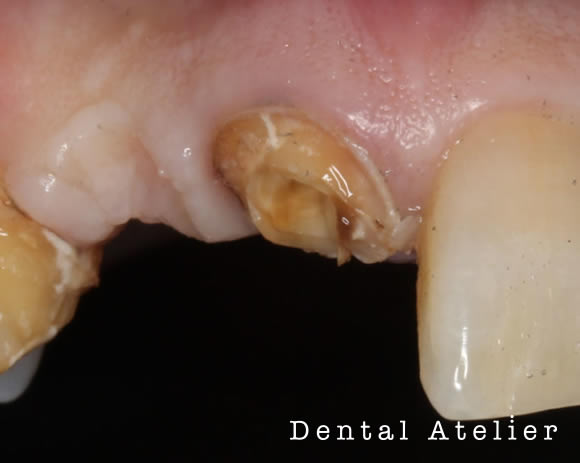

根の先の膿を診断され、治療を「抜歯」と言われた患者さんが来院されました。

当院にて、マイクロスコープ下で自費の精密根管治療を行いました。

MTAセメントにて根管充填を行い、5か月後のCT写真です。

初診時

5か月後

初診時、矢印の先にあった黒い影(膿の袋)が5か月後には無くなり、溶けた骨が再生してきています。

完全に骨化するには半年以上かかる見込みです。